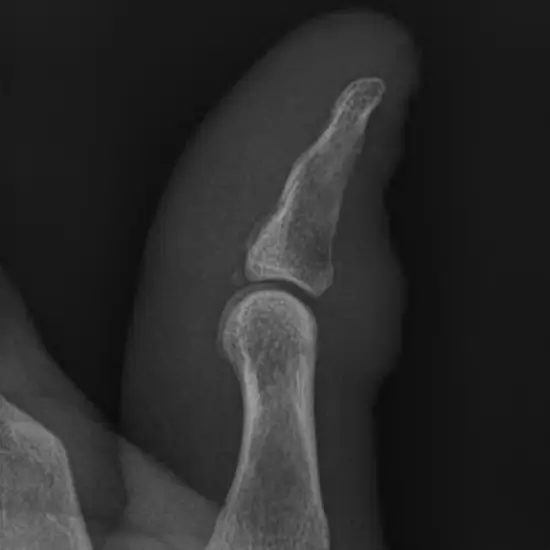

What is the NCCT Thumb?

NCCT Thumb is a non-contrast computed tomography thumb is a plain scan to visualize the thumb and its pathology.

Why is NCCT Thumb done?

Doctors recommend this test for many conditions like:

• Fracture

• Tumors

• Pain

• Tenderness

In this examination, you need to lie prone on a table and affected hands are placed in the centre of the scanning table and the head can rest on the other arm sides then scans are performed. No contrast medium /dye is used in this radiological examination.